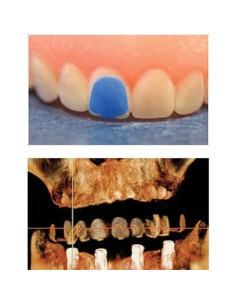

4. Equipamiento Odontológico

6. Prótesis Dental

Modelo de Diente Typodont para Implantes Dentales 2001P Modelo de Diente Typodont para Implantes Dentales 2001P 2

Modelo de Diente Typodont para Implantes Dentales 2001P

Modelo de Implante Dental ANNWAN 4 Veces Removible para Educación Modelo de Implante Dental ANNWAN 4 Veces Removible para Educación 2

Modelo de Implante Dental ANNWAN 4 Veces Removible para Educación

Modelo Dental Sobredentadura Inferior Smile1000 2 Implantes Modelo Dental Sobredentadura Inferior Smile1000 2 Implantes 2

Modelo Dental Sobredentadura Inferior Smile1000 2 Implantes

Modelo Dental Sobredentadura Inferior Smile1000 4 Implantes Modelo Dental Sobredentadura Inferior Smile1000 4 Implantes 2

Modelo Dental Sobredentadura Inferior Smile1000 4 Implantes